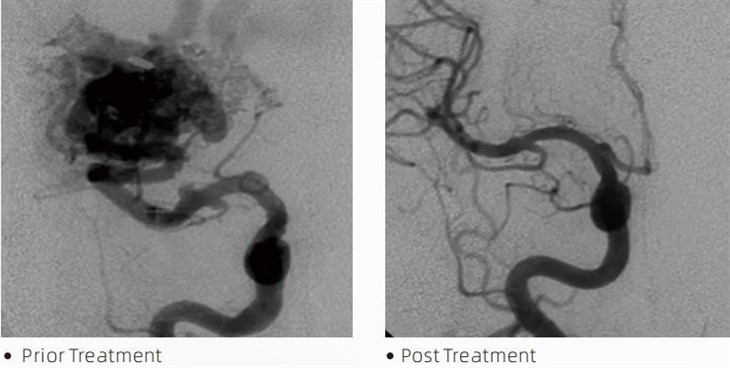

लावाटीएमएम्बोलिक ग्लू एक चिकित्सा उपकरण है जिसका उपयोग इंटरवेंशनल न्यूरोरेडियोलॉजिस्ट द्वारा सेरेब्रल एन्यूरिज्म, धमनीविस्फार संबंधी विकृतियों और ट्यूमर जैसी स्थितियों के इलाज के लिए न्यूनतम इनवेसिव प्रक्रियाओं के दौरान किया जाता है। लावा एम्बोलिक गोंद सुरक्षा, उपयोग में आसानी और प्रभावशीलता के मामले में चिकित्सा पेशेवरों और रोगियों को समान रूप से कई लाभ प्रदान करता है। लावा रक्त वाहिकाओं को जल्दी और कुशलता से बंद करने में सक्षम है। इस प्रक्रिया में गोंद को सीधे लक्षित पोत में इंजेक्ट करना शामिल है, जहां यह पोलीमराइज़ हो जाता है और एक कास्ट-जैसे द्रव्यमान में कठोर हो जाता है जो एन्यूरिज्म या विकृति को भर देता है। फिर यह घाव में रक्त के प्रवाह को प्रभावी ढंग से रोक देता है, इसे फटने से बचाता है और स्थायी क्षति या स्ट्रोक के जोखिम को कम करता है। लावा में लावा-12, लावा-18 और लावा-34 शामिल हैं। प्रत्येक फॉर्मूलेशन विशिष्ट नैदानिक आवश्यकताओं को पूरा करने के लिए डिज़ाइन किया गया है। लावा-18 सामान्य उपयोग के लिए मानक फॉर्मूलेशन है। लावा-34 उच्च प्रवाह वाले जहाजों के लिए उच्च-चिपचिपापन वाला गोंद है। जबकि लावा-12 की चिपचिपाहट कम होती है और यह अधिक प्रवाह योग्य होता है, जो डिस्टल माइक्रोवेसल्स के लिए अनुमति देता है। इन विकल्पों के साथ, इंटरवेंशनल न्यूरोरेडियोलॉजिस्ट इष्टतम परिणाम सुनिश्चित करने के लिए उपयुक्त लावा फॉर्मूलेशन का चयन कर सकते हैं। लावा की सबसे उल्लेखनीय विशेषताओं में से एक इसके गैर-चिपकने वाले गुण हैं। यह पदार्थ विशेष रूप से लक्षित क्षेत्र तक पहुंचने तक स्थिर रहने के लिए तैयार किया गया है। इस विशेषता का मतलब है कि लावा एम्बोलिक गोंद को धमनी के भीतर सटीक रूप से रखा जा सकता है और आसपास के ऊतकों से चिपके या जुड़े बिना वहां रह सकता है।